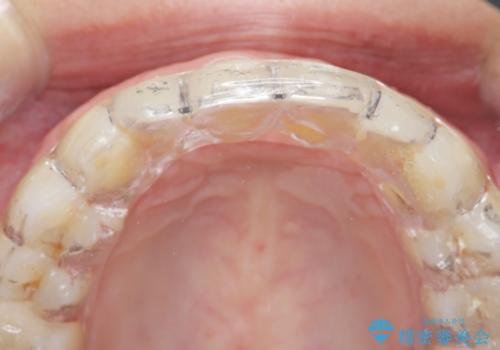

型取り(上下)をして自費のナイトガードを作製しました。

保険のナイトガードと比べると割れにくくて、噛み合わせの歯と調整を行うために歯が変に負担がかかる事なく歯ぎしりや歯の破折を予防することができます。